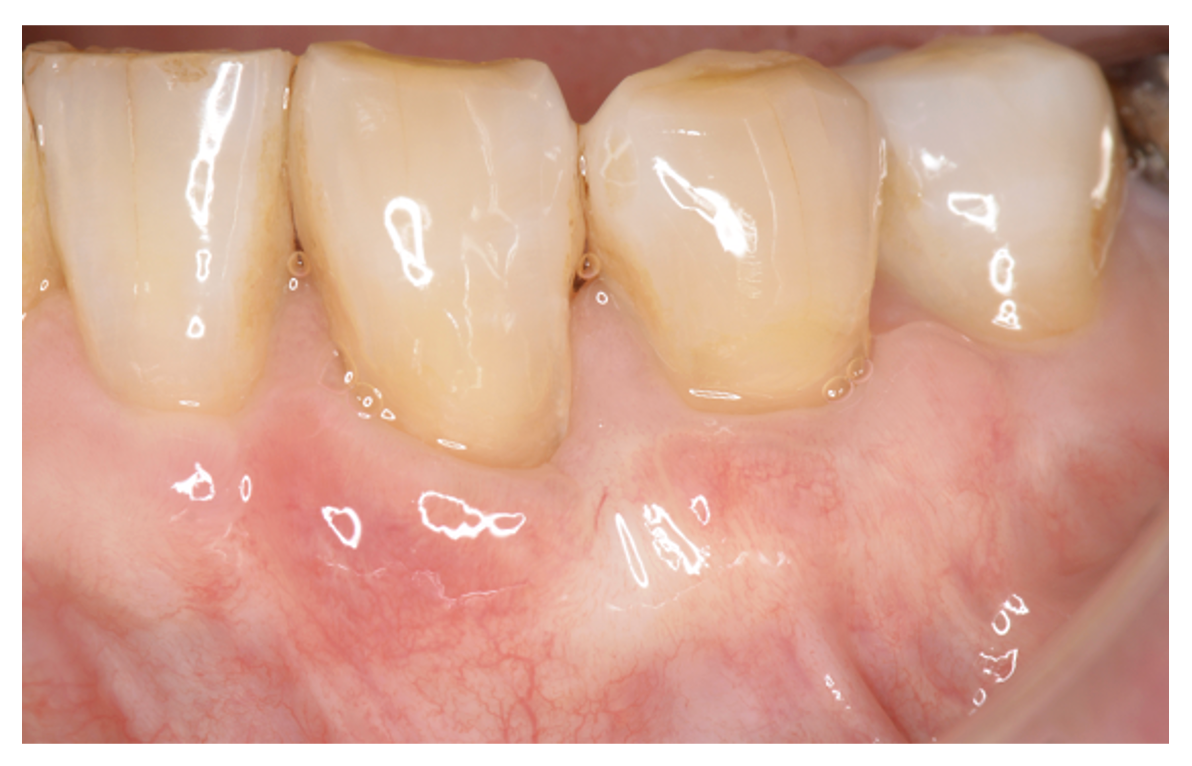

下がった歯茎を元通りにしたい

術前

術後5年

| 主訴 | 歯茎が下がってきている。 歯磨きもしにくいし、見た目も気になる。 このまま下がって歯が抜けないか心配。 |

| 治療内容 | ブラッシング指導、歯石の除去 歯周形成手術(結合組織移植術) →歯茎の再生手術 |

| 治療期間 | 2ヶ月 術後3ヶ月経過してメインテナンスに移行 |

| 費用 | 77,000 *対象歯の本数により異なります。 |

| リスク・副作用 | 手術部位が2箇所になります。移植片を採取する部位(上あごの歯肉)と移植する部位(歯肉退縮部位)。特に採取部位では疼痛や出血を伴います。また、退縮量が大きい場合や症例によっては2度に分けて手術を行う場合があります。 |